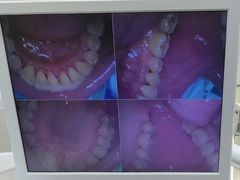

• 牙博士口腔品牌连锁(杨浦店)

• -牙博士口腔品牌连锁(杨浦店)

莫失莫忘 | 24-06-21

知知美好的小宾 | 24-06-20